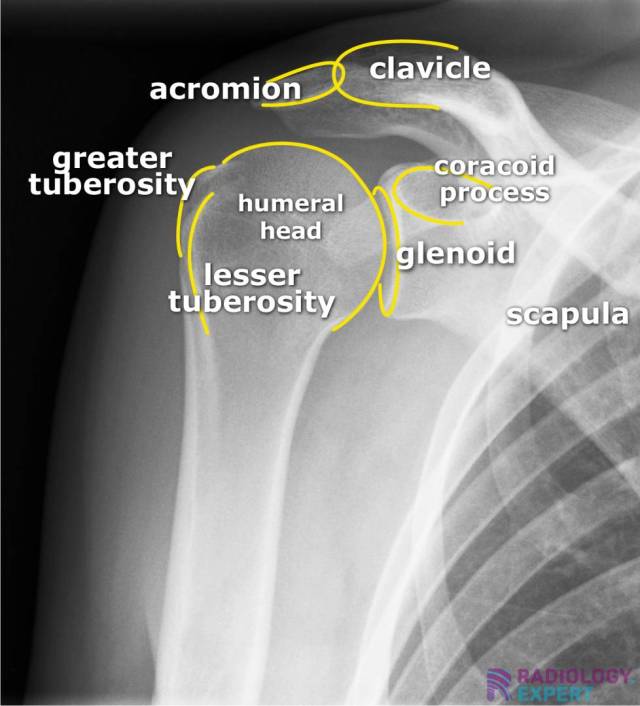

The supraspinatus muscle originates from the supraspinous fossa of the scapula, and its tendon courses through the subacromial space, inserting onto the superior facet of the greater tuberosity of the humerus. Codman's critical avascular zone is located 1 cm proximal to the distal insertion, where repetitive mechanical tension and relative hypovascularity predispose to fibrillar degeneration and eventual rupture.

Biomechanically, the supraspinatus acts as the initiator of glenohumeral abduction (0–15°), working synergistically with the deltoid. As a component of the concentric compression mechanism, it stabilizes the humeral head against the glenoid during movement. Its dysfunction alters scapulohumeral rhythm and predisposes to secondary injuries of the infraspinatus tendon, long head of biceps brachii, and glenoidal labrum.